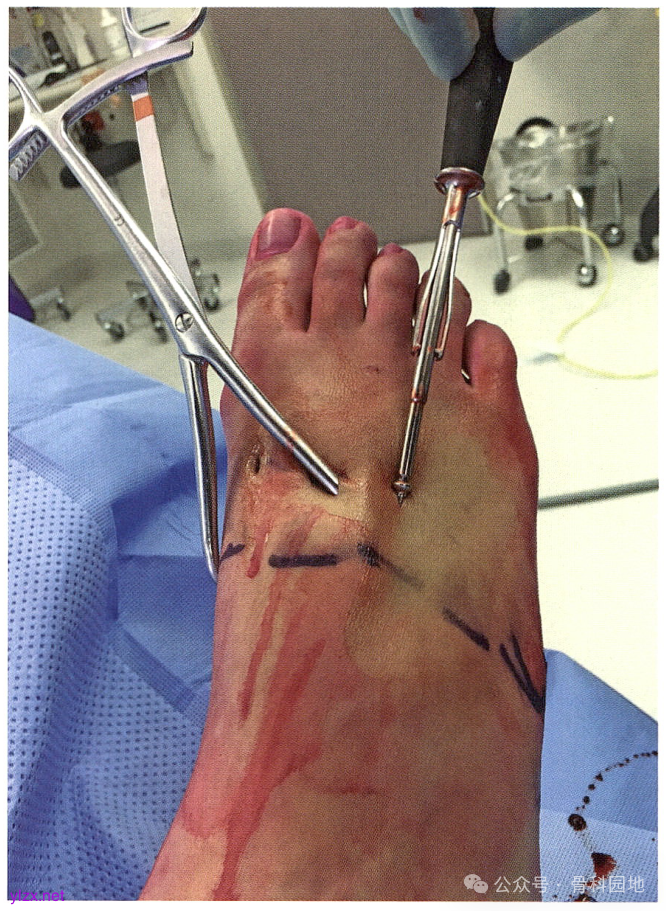

大多数损伤的第2MT都是向外半脱位的。将第2MT基底复位到第1MT基底外侧和内侧楔骨外侧关节面形成的凹陷中。在内侧楔骨的内侧皮质和第 2 MT基底外侧经皮放置一个中号复位钳,然后钳夹复位。